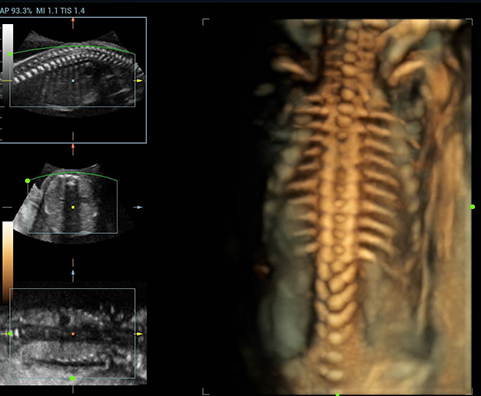

Позвоночник эмбриона, 3D